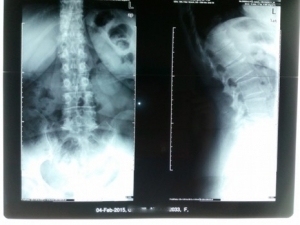

Πλάγια Σπονδυλική Στένωση Ο4-Ο5-Ι1+Σπονδυλολίσθηση Ο4-Ο5, Σπονδυλοδεσία-Ευρεία πεταλεκτομή Ο4-Ο5-Ι1

Ασθενής 55 ετών προσήλθε με συμπτώματα χρόνιας οσφυαλγίας και σοβαρό ριζιτικό πόνο κατανομής 05 ρίζας αριστερά (πόνος στην έξω επιφάνεια της γαστροκνημίας αρ.) και Ο4 ρίζας άμφω (πόνος γύρω από την περιοχή των γονάτων) χωρίς ύφεση παρά τη μακροχρόνια συντηρητική θεραπεία. Η Ασθενής παρουσίαζε και συμπτωματολογία νευρογενούς διαλέιπουσας χωλότητας κατά τη βάδιση. Ο έλεγχος με MRI κατέδειξε πλάγια σπονδυλικη στένωση Ο4-Ο5-Ι1 άμφω(Εικ.2,3,4).Ο ασθενής υποβλήθηκε σε οπίσθια σπονδυλοδεσία 04-05-Ι1 και ευρεία πεταλεκτομή 04-05-Ι1 με αποσυμπίεση των 04-05-Ι1 ριζών άμφω (ΕΙκ.5).Το αποτέλεσμα κρίνεται επιτυχές.